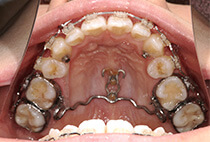

しっかり前歯を下げるために、インプラントアンカーを使用してコントロールしました。

治療前